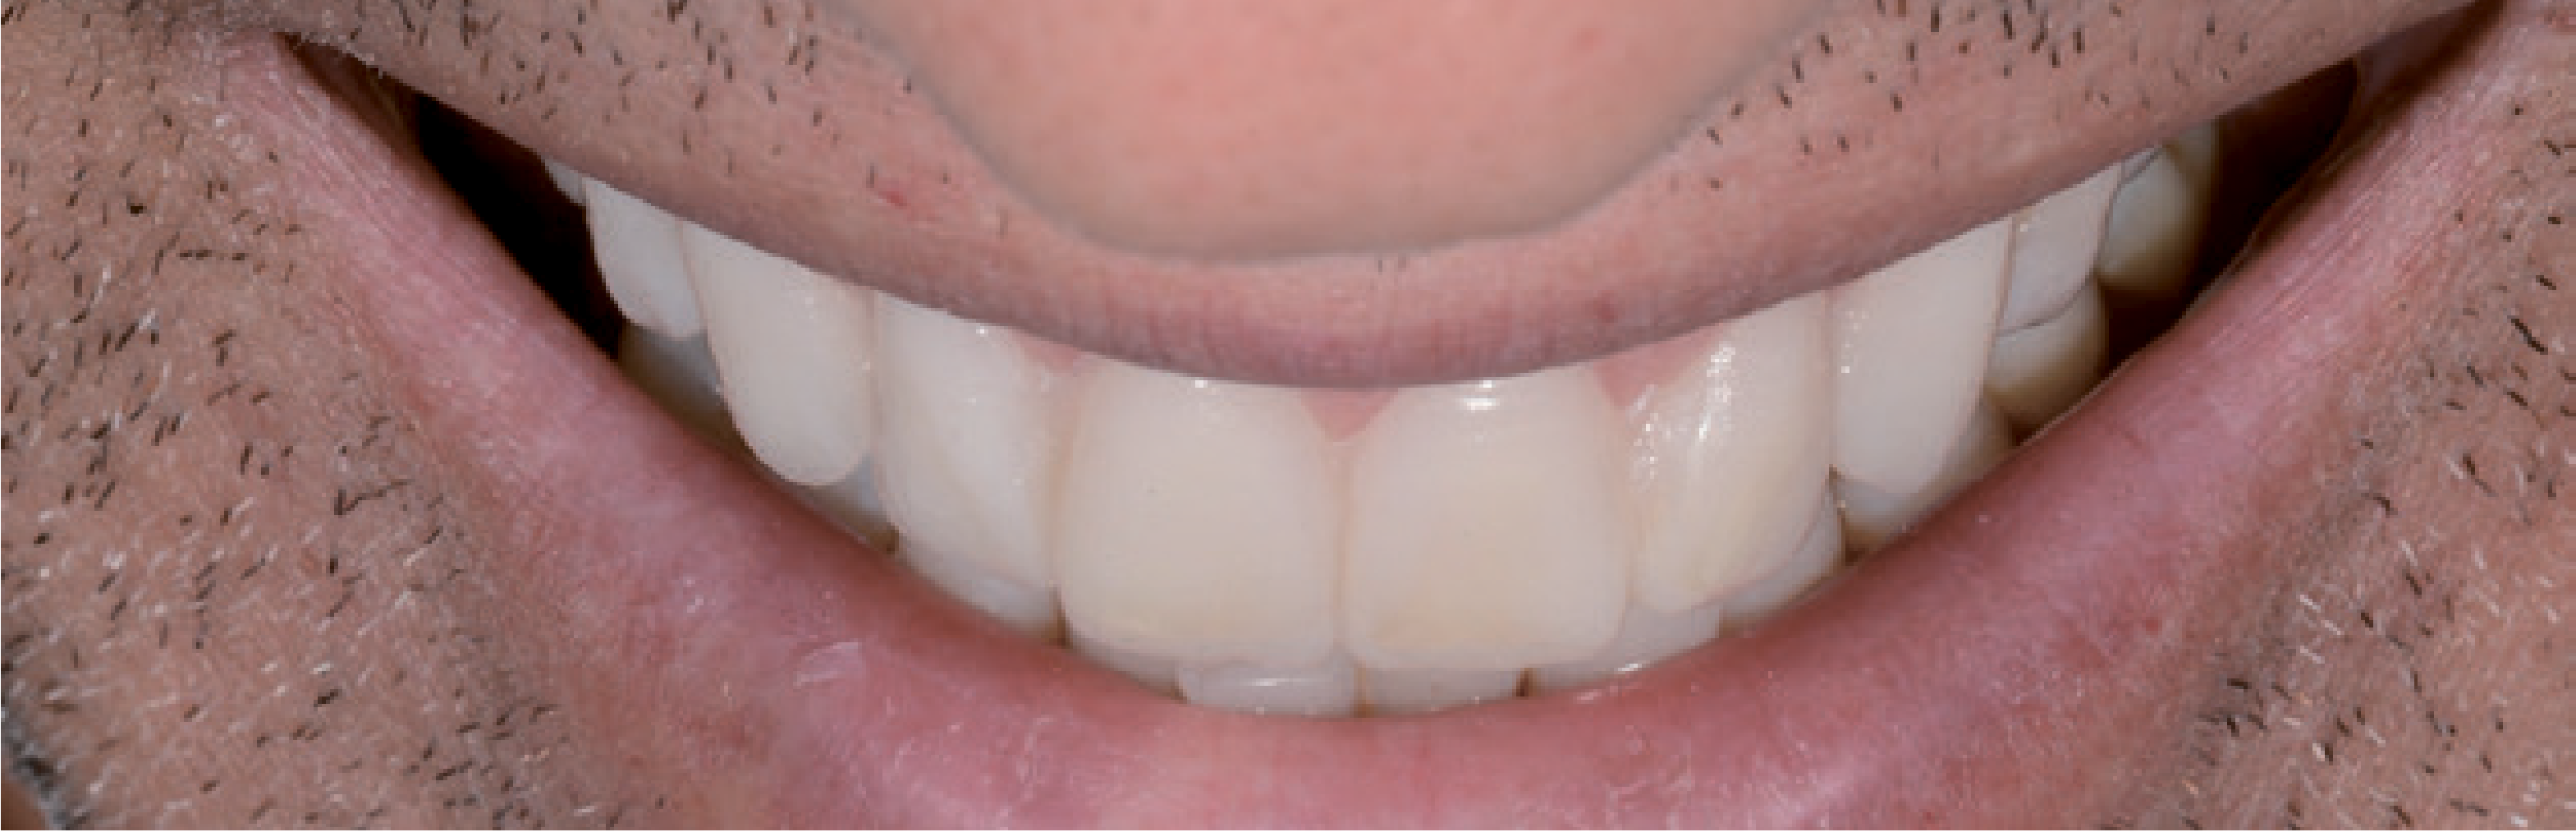

Навіть досить кваліфіковані стоматологи зовсім не завжди вирішуються використовувати вініри для естетичної реставрації. Вони бояться не отримати бажаний естетичний результат, адже пацієнти дуже вимогливо ставляться до такої процедури, оскільки вони змушені чимало за неї заплатити. Психологічна сторона, пов'язана з естетичною зоною, є непередбачуваним фактором ризику. Завдяки двоетапній техніці прямого й непрямого mock-up естетичний результат можна обговорити з пацієнтом, а потім і реалізувати його за участю пацієнта. Коли модель mock-up виглядає достатньо переконливо для стоматолога й пацієнта, вона використовується як якісний орієнтир для отримання задовільного естетичного результату. Далі препарування виконується виключно в межах емалі – для надійної фіксації реставраційної конструкції адгезивним цементом на тривалий термін. З цієї причини згодом, щоб створити оптимальне з’єднання, поглиблення не препарували. У цьому випадку ці ділянки непомітні крізь лінію посмішки, і пацієнт не захотів, щоб контури виправляли мікрохірургічним шляхом. В інших випадках оптимізувати естетичний вигляд м'яких тканин можна за допомогою вільного слизового трансплантата. Новий сагітальний різцевий шлях був створений за допомогою вінірів, щоб не допустити впливу неконтрольованих зусиль. Вночі ж щелепно-ротовий апарат і реставраційні конструкції були захищені за допомогою верхньощелепної ортопедичної капи. Активне спілкування і взаємодія стоматолога з пацієнтом спочатку передбачає виконання додаткової роботи, проте допомагає швидко отримати прогнозований результат і виключити непередбачені витрати коштів і часу, а також непотрібний стрес і розчарування (мал. 21 і 22).